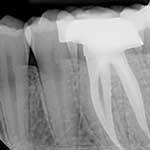

ΕΝΔΟΔΟΝΤΙΑ

Ενδοδοντία

Η ενδοδοντία, ή απονεύρωση όπως είναι κοινά γνωστή, έχει ως στόχο τη διάσωση ταλαιπωρημένων δοντιών με σκοπό να διατηρηθούν στη στοματική κοιλότητα του ασθενή. Κατά τη διάρκεια της θεραπείας, καθαρίζεται όλη η τερηδόνα και το σαπισμένο δόντι και προετοιμάζεται κατάλληλα για να δεχτεί το τελικό υλικό.